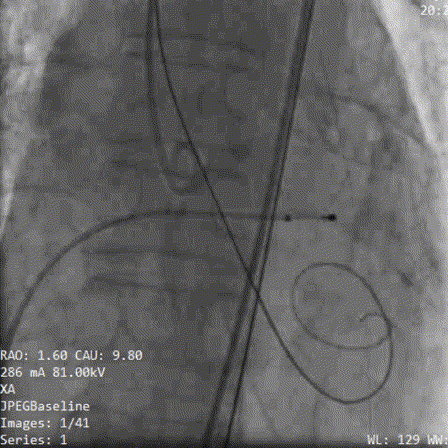

术中影像:

2.初始定位